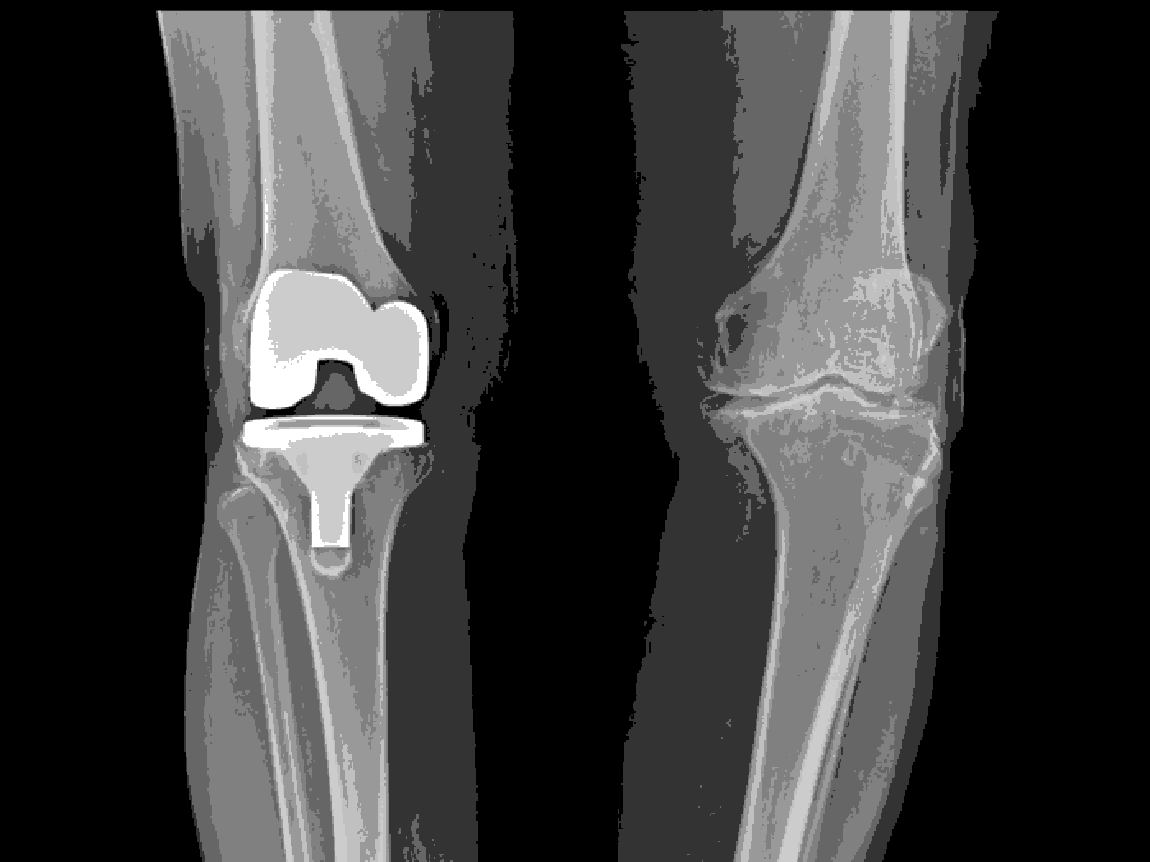

When to Consider Surgery

Surgery may be considered if Pain severely limits daily activities Inability to get out of bed, go to the washroom.

Considered only for severe cases after optimal non-surgical care;Arthroscopy is not recommended for uncomplicated OA